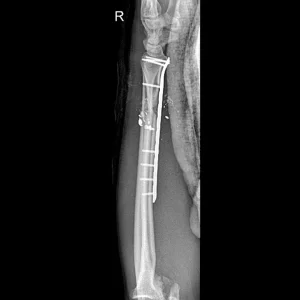

Placas para radio distal

RÁDIX Large

Rádix Plus

Materiales

Titanio para implantes

Presentación Set

Large Derechas e Izquierdas 9 Orificios.

Para usar con:

» Tornillo Cortical Autotarrajante 2.7 mm – Titanio

» Tornillo de Bloqueo 2.4mm – Titanio